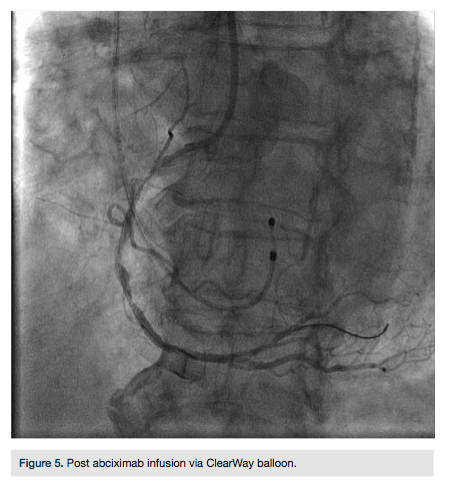

The right radial artery was prepped and draped in sterile fashion, then accessed with a 6 French (Fr) Glidesheath (Terumo). The right antecubital vein was accessed by the nurse prior to the patient’s arrival to the lab and changed (after sterile prep followed by betadine solution) to a 5 Fr Glidesheath (Figure 2). The transvenous pacemaker was advanced  into the right ventricle (Figure 3). Following placement of the pacemaker and capture, a Judkins right (JR) 4 6 Fr guide was used to engage the right coronary artery. Angiography demonstrated a proximal right coronary artery occlusion with TIMI-0 flow (Figure 4). After administration of bivalirudin (Angiomax, The Medicines Company), a Runthrough wire (Terumo) was passed distally. A 1.0 x 10 mm ClearWay balloon (Atrium Medical) was advanced to the lesion and intracoronary abciximab (ReoPro, Eli Lilly & Co.) was administered. Following drug administration, there was improved flow and evidence of a more focal obstruction (Figure 5). A 3.0 x 15 mm Integrity bare metal stent (Medtronic) was deployed at 11 atm with no angiographic residual stenosis and restoration of TIMI-3 flow (Figure 6).  Following revascularization of the right coronary artery, the guide was advanced into the left ventricle to calculate the left ventricular end diastolic pressure (LVEDP) and perform ventriculography (estimated ejection fraction was 55% with mild inferobasal hypokinesis noted on hand injection.  No significant transvalvular gradient was noted on pull-back). A diagnostic Judkins left (JL) 3.5 catheter was then used to engage the left coronary system. Angiography revealed a 90% proximal left anterior descending coronary artery (LAD) stenosis and intermediate disease of the circumflex (Figure 7).  The patient was started on ticagrelor (Brilinta, AstraZeneca) and aspirin, and transferred to the unit. The pacemaker was removed after the patient regained sinus rhythm. She was discharged home after 48 hours with plans for staged intervention of the LAD.